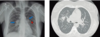

Sindrome da Embolia Gordurosa